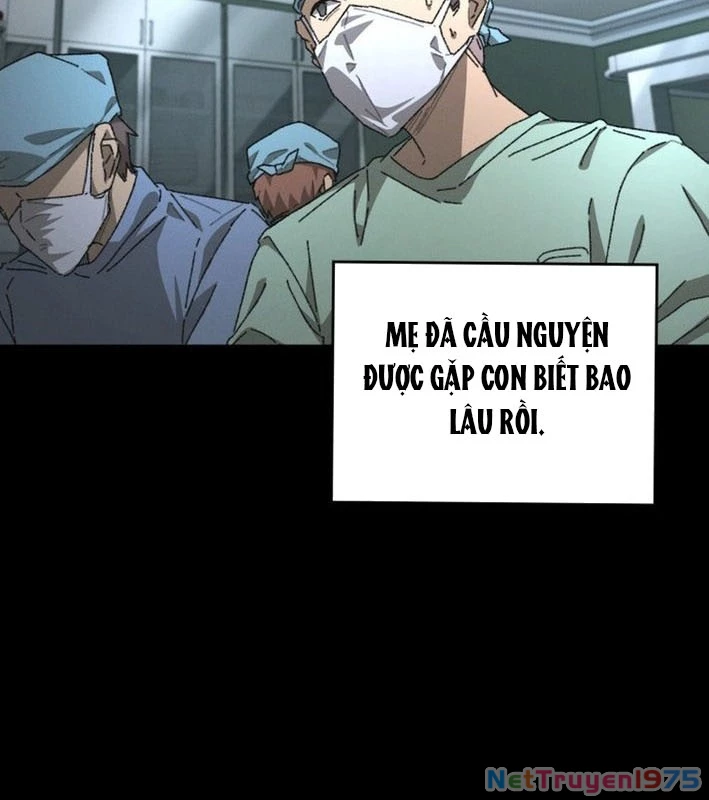

Kẻ Chôn Cất Quái Vật - Chapter 1